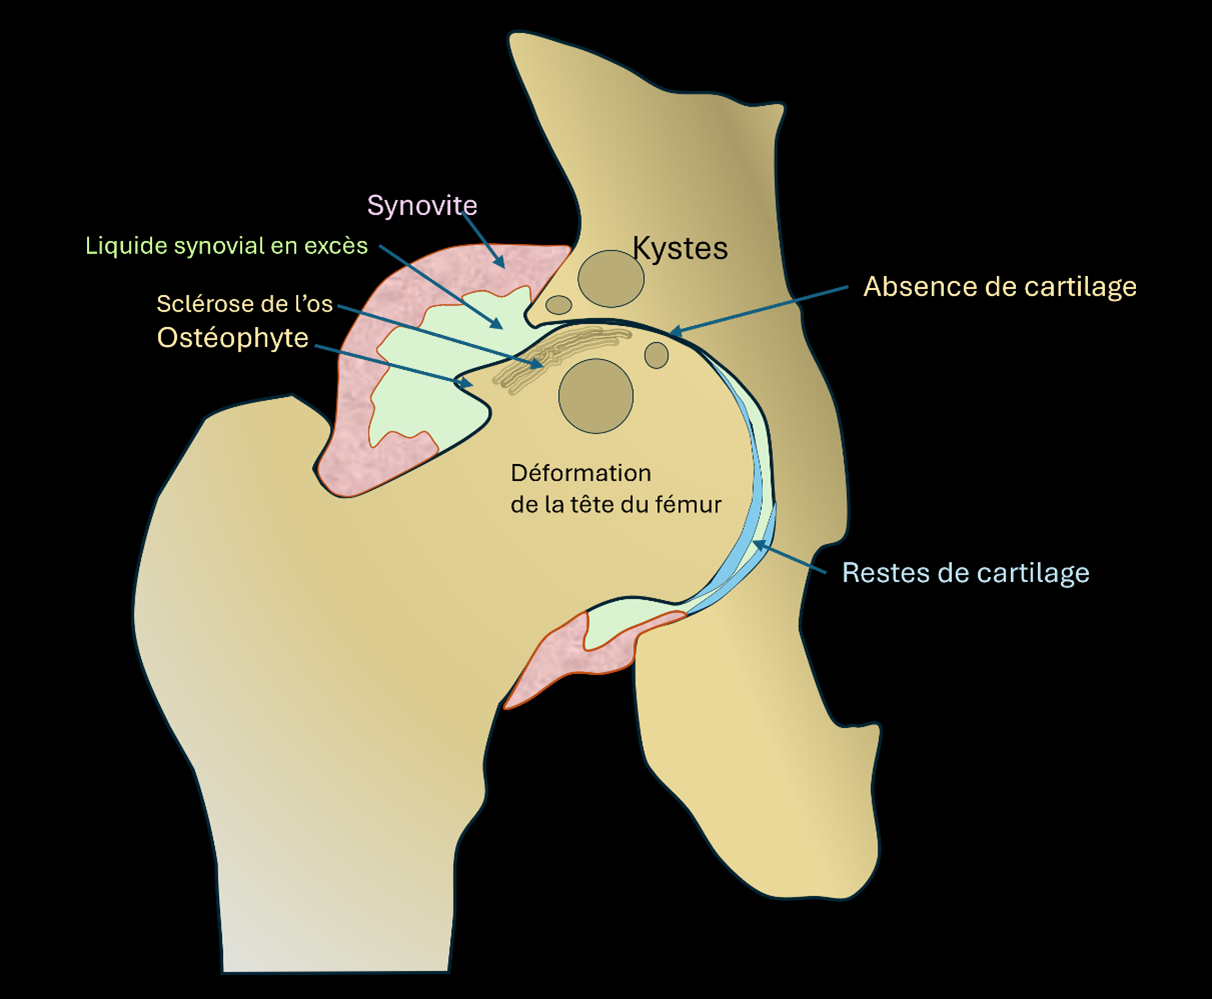

L’arthrose de hanche (coxarthrose) correspond à :

- Une usure progressive du cartilage.

- Des modifications de l’os.

- Des phénomènes biologiques avec une inflammation locale plus ou moins marquée et une production excédentaire de liquide articulaire.

Cela provoque une raideur, des douleurs au mouvement et/ou au repos, une boiterie.

représentation schématique d’une hanche avec de l’arthrose (coxarthrose) :

Les éléments caractéristiques visibles sur la radiographie sont :

-> L’amincissement puis la disparition partielle ou complète du cartilage.

-> La déformation progressive de la tête fémorale.

-> La formation de kystes osseux.

-> La formation d’ostéophytes (excroissances osseuses).

-> Une densification ou sclérose de l’os.

Les éléments biologiques non visibles sur la radiographie sont :

-> Une synovite (épaississement de la membrane synoviale recouvrant l’intérieure de la capsule articulaire de la hanche).